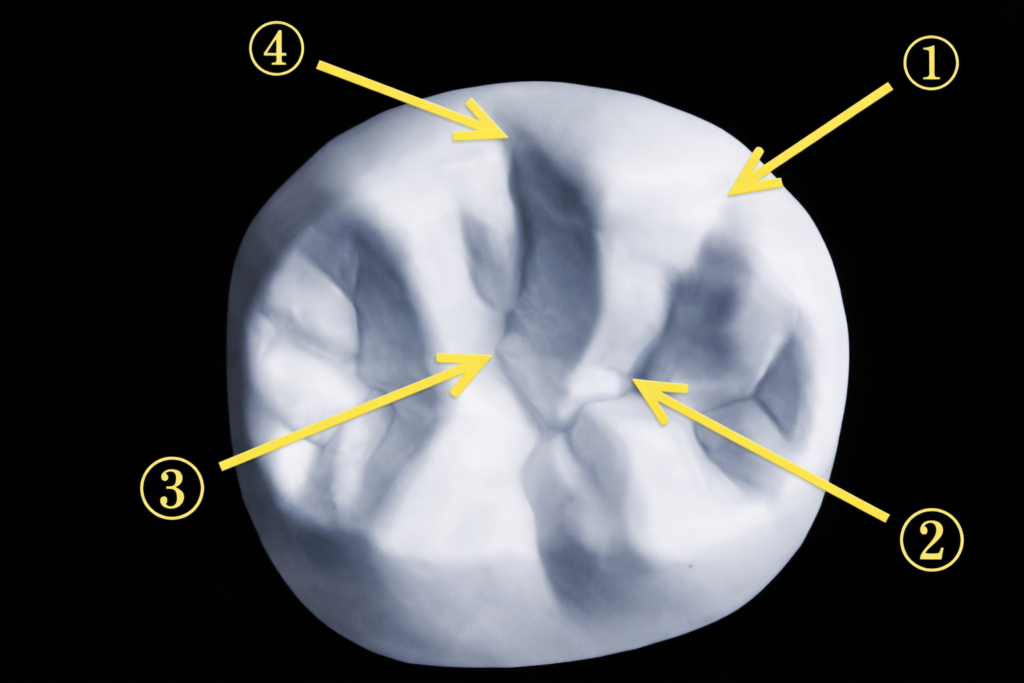

午前-54

上下顎右側第一大臼歯の石膏模型の咬合面観の写真を別に示す。 Angle 1級で、上顎右側第一大臼歯の矢印で示す部位が接触するのはどれか。1つ選べ。

a. ①

b. ②

c. ③

d. ④

解答を見る

d